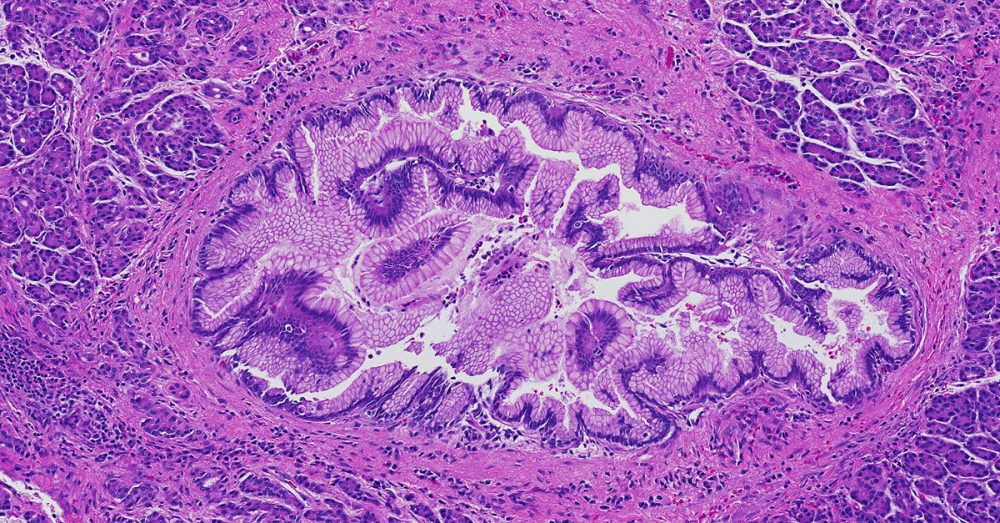

Low-grade pancreatic intraepithelial neoplasia encompasses three older terms- PanIN-1A, PanIN-1B and PanIN-2.